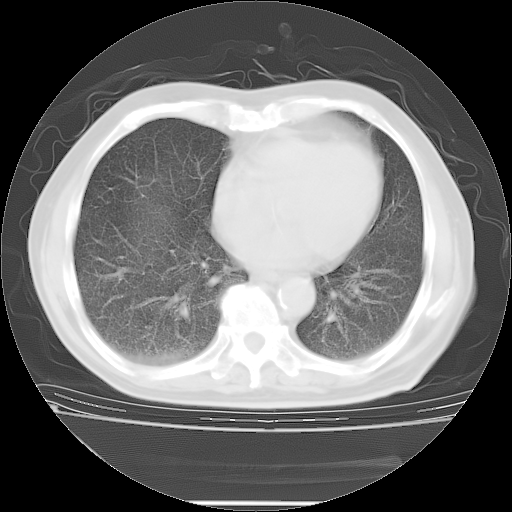

5月9日肺部CT(在4月27日齐鲁医院肺部CT描述部分肺组织磨玻璃样改变,12天后肺组织广泛磨玻璃样改变)

2009年5月9日肺部CT

大致读了系列胸部CT:纵隔窗无明显异常,肺窗:从4、27至今:主要是双肺中下野外带可见毛玻璃样改变,目前处于急性肺泡炎阶段,至于原因考虑1、结替组织或胶原血管性疾病所致?2、恶性疾病如恶组在肺部所致的表现或细支气管肺泡癌?3、药物或其它原因如肺蛋白沉着症所致肺泡炎目前不太可能?总之,明天就去请我院的呼吸科、感染科、血液科和临免专家会诊哈。